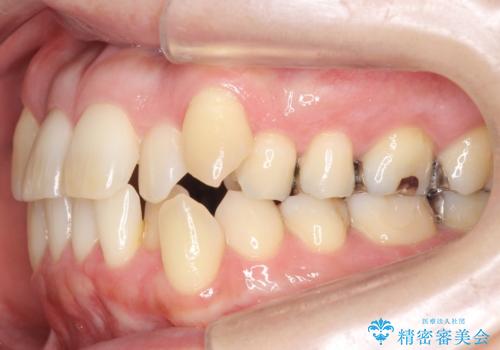

40代の矯正 八重歯を綺麗に

上の前歯が内側に入っているクロスバイトは、笑った時に影になってしまい、かなり目立ちます。

内側に入っている前歯を外に出すだけで劇的に印象が変わります。